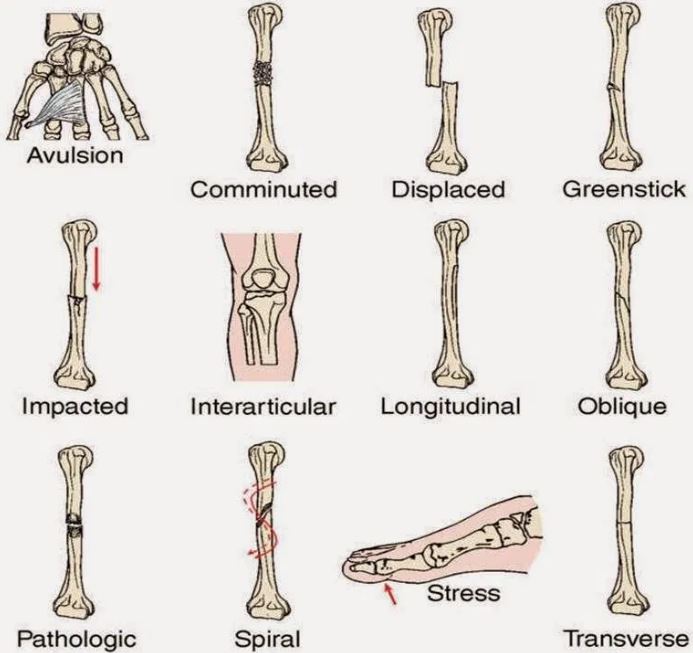

Jenis Dan Kategori Tulang Patah

Jenis Dan Kategori Tulang Patah

Fraktur - Jenis û Penyebab dan Pengobatan - IDN Medis

Fraktur - Jenis û Penyebab dan Pengobatan - IDN Medis

Bab 5 luka & patah

Bab 5 luka & patah